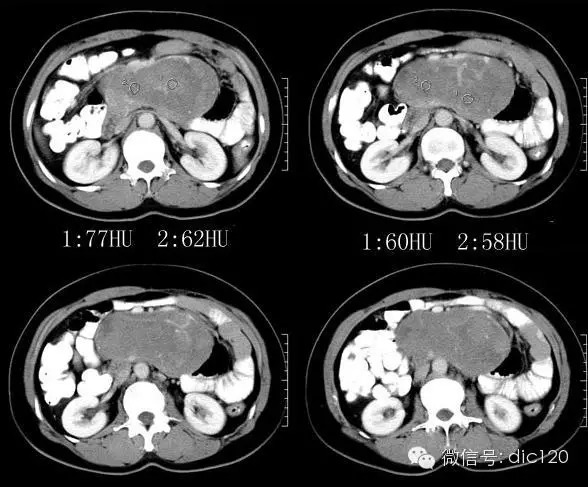

【影像图片】

平扫:腹膜后区域可见形态略不规则的类椭圆形肿块影,密度比较均匀;边缘大部分清晰,与主动脉和部分肠壁的边缘模糊,且脂肪间隙消失;周边脂肪的密度比较均匀;肠系膜上动脉,肠系膜上静脉,肠系膜及肠管向前方和侧方受压移位明显;腹腔内未见明显的肿大淋巴结。增强:动脉期肿块强化并非明显,但可见增多、增粗、迂曲的供血血管影;静脉期肿块强化的略明显,且略有不均匀,可见形态不规则的低密度轻微强化或者不强化的区域。

3.增强渐进明显强化,内部示粗大较规则血管影;定位:后腹膜;定性:低度恶性间叶组织来源肿瘤>神经源性肿瘤。